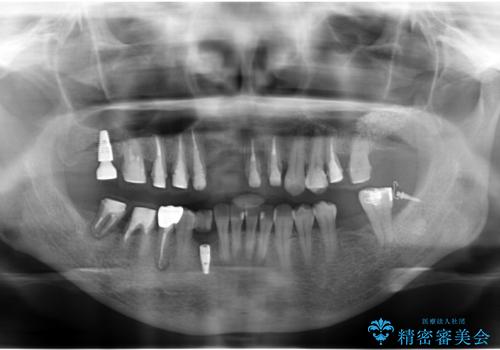

- 全体的な虫歯治療、根管治療、および歯周病治療を行いました。

歯周病治療につきましては歯周ポケット除去のために歯周外科処置(APF)を行っています。

左下6の欠損については左下7はワイヤー部分矯正でアップライトを行い、補綴スペースを確保しています。

右下犬歯は歯周病の進行が重度のため、やむなく抜歯をし、骨増生後にインプラント埋入を行っています。

根管治療は横浜桜木町歯科 大元先生が担当しました。

右下7の根管治療および再植は銀座院 林先生が担当しています。(抜歯は希望されなかったため、再植を行い、現在経過観察中です。)